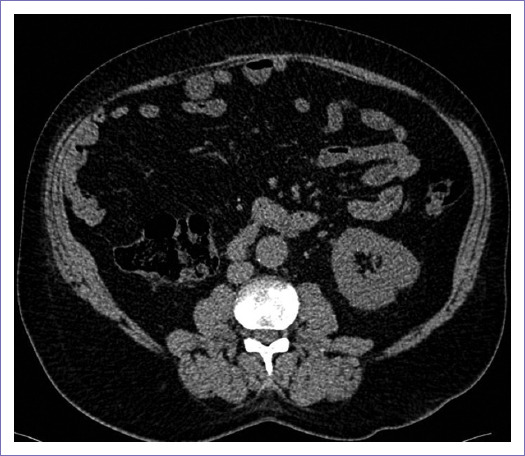

Antecedente de inicio con dolor tipo cólico renoureteral en fosa renal derecha con diaforesis, con hematuria al día siguiente y expulsión de lito de color claro, estrellado. Se realizó una tomografía abdominal, donde se encontró tumoración renal en polo inferior derecho con características de malignidad, de tamaño 120 x 80 mm, sin presencia de ganglios periféricos ni involucro vascular, motivo por el cual ingresó programado para nefrectomía laparoscópica radical derecha dos meses después de inicio de síntomas, con hallazgo de tumor renal a expensas del polo inferior, con tamaño total aproximado de 25 x 15 x 15 cm y diagnóstico histopatológico de cáncer renal de células claras Furhman 3 (pT3aNxMx), con invasión al seno renal con bordes quirúrgicos de arteria, vena y uréter negativos, sin tratamiento adyuvante y seguimientos cada tres a seis meses posteriores (Fig. 1).